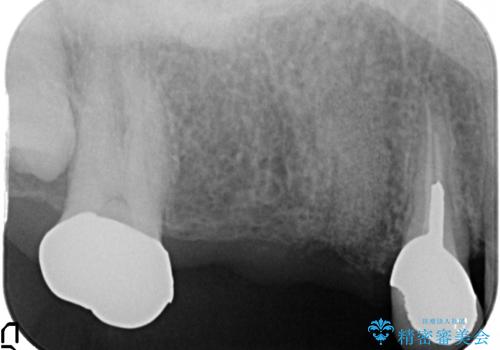

- 右上のブリッジでものを咬むと違和感があり、歯茎に膿の出口もできているので診て欲しいといらっしゃった方の症例です。

右上の567ブリッジを外したところ、右上5は歯根破折により保存不可能だったため、右上56部にインプラントを埋入し欠損補綴を行いました。

また右上5部に関しては抜歯時に歯槽堤保存術(抜歯窩に人工骨の填入を行う手術)を行い、骨の欠損を最小限に止めています。